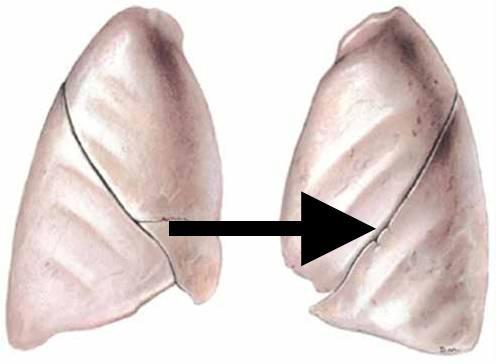

Horizontal fissure (of right lung)

Left/right oblique fissue (of lung)

arrow

Upper/middle/lower lobe (of lung)